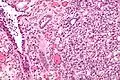

| Micrograph of a nephrogenic adenoma. H&E stain. | |

Nephrogenic adenomas are diagnosed under the microscope by pathologists. Microscopically the tumor shows closely packed small tubular structures in edematous stroma. The tubules show considerable variation in size and shape resembling convoluted tubules of the kidney. The single layer of cells lining the tubules are cuboidal with a scant to moderate amount of cytoplasm. In some areas they may have a hobnail appearance. [2]